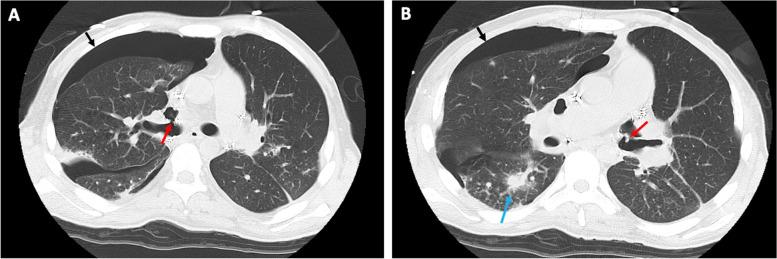

A 25-year-old man with idiopathic pulmonary arterial hypertension underwent a bilateral lung transplant. The patient developed bilateral bronchial dehiscence. Open reanastomosis was not successful, and air leakage recurred under low positive pressure ventilation. VV ECMO was established to maintain oxygenation with spontaneous breathing until both dehiscence were closed by adhesions.